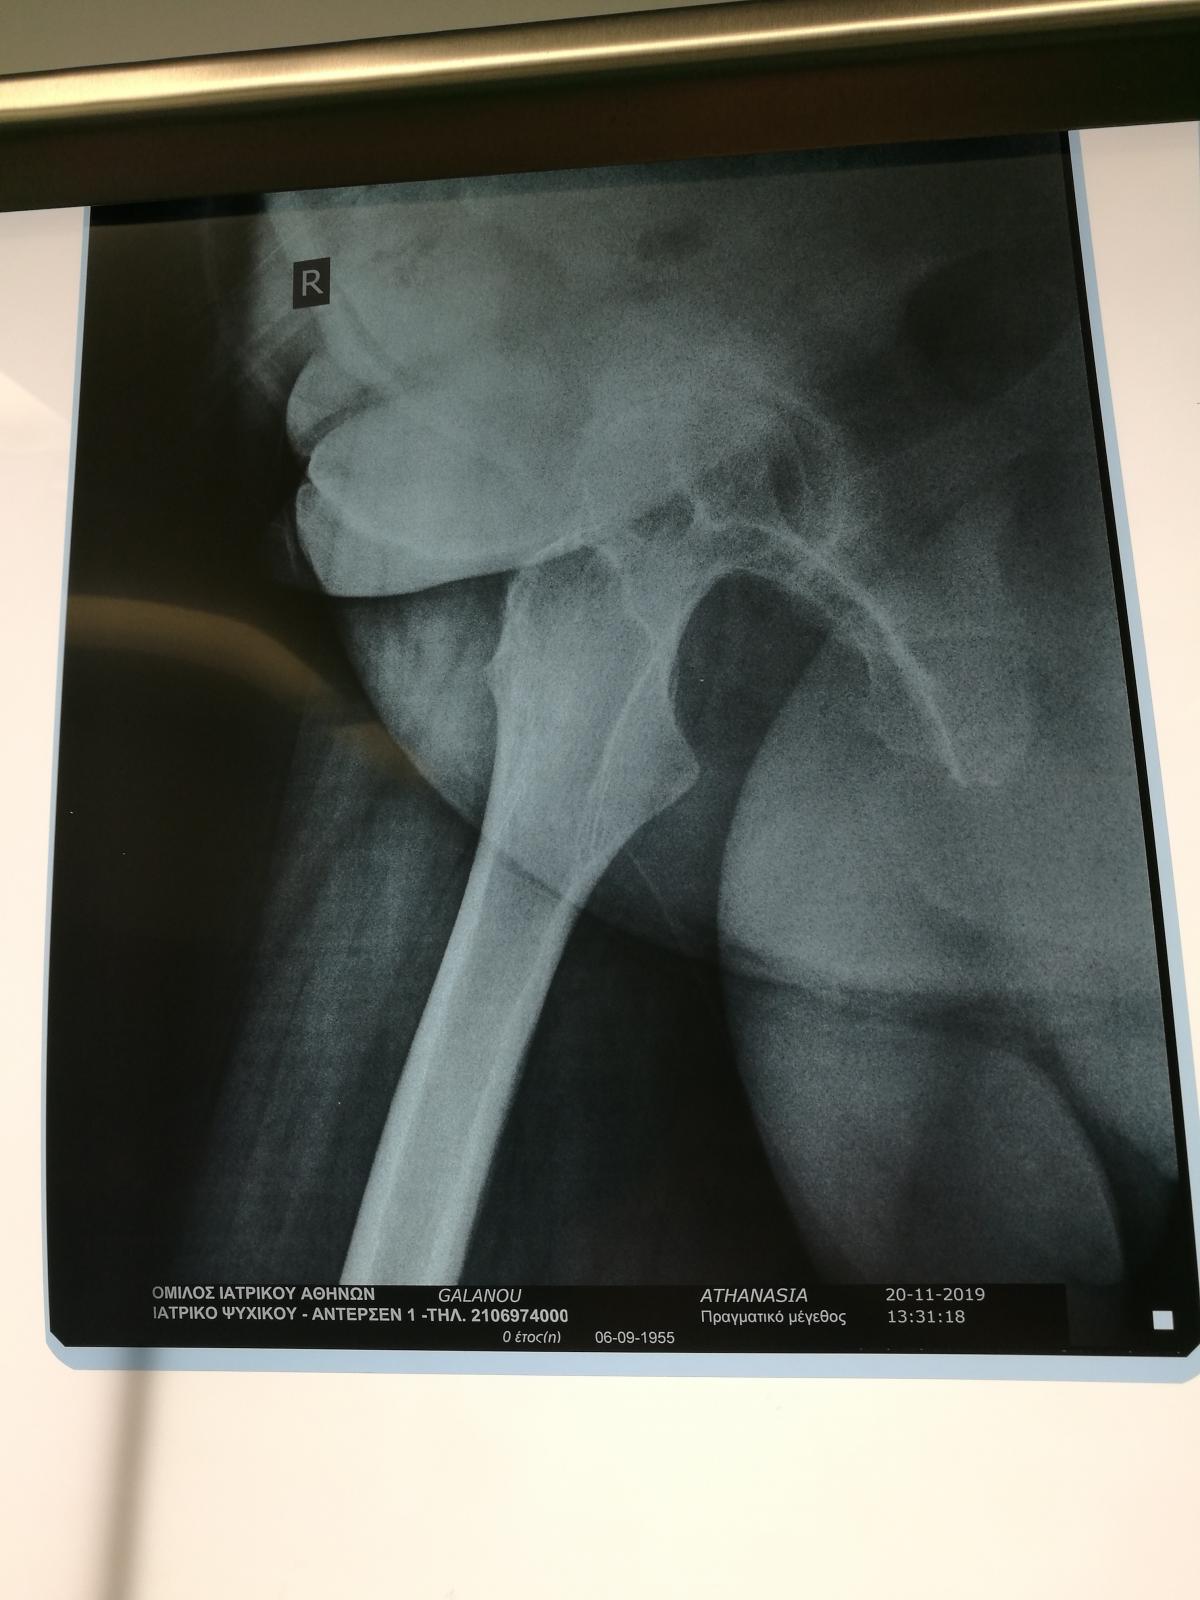

Стажування в приватній клініці у професора Христодулоса Афіни Греція листопад 2019

Компанія Lima надала стажування в ортопедичній приватній клініці місті Афіни Греція в листопаді 2019 року. Ендопротезування кульшового суглоба протезами компанії Lima малоінвазивним передньо-латеральний доступом у професора Христодулоса.